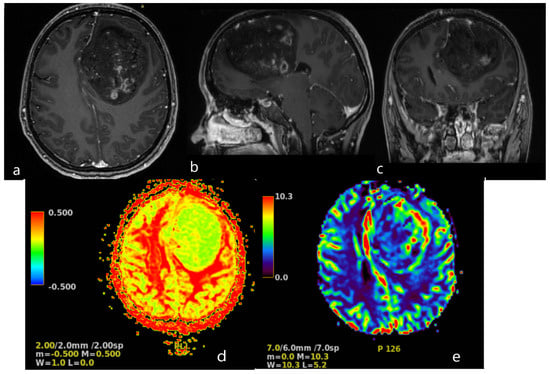

A magnetic resonance imaging (MRI) scan showed a massive (83 × 58 × 62 mm) lesion in the left frontal lobe, invading the corpus callosum, with heterogeneous hyperintense T2 and FLAIR signals, hypointensity on T1-weighted images, and peritumoral edema. After gadolinium administration, the lesion showed heterogeneous enhancement on T1-weighted imaging. The preoperative radiological diagnosis was high-grade glioma (Figure 2).

Figure 2. Brain MRI. Axial (a), sagittal (b) and frontal (c) contrast T1−weighted image demonstrates a large (83 × 58 × 62 mm) heterogeneously enhancing tumor in the left frontal lobe, results in a midine shift to the right side to 12 mm. Arterial Spin Labeled MRI Perfusion Imaging (d,e): elevated regional Cerebral blood perfusion (rCBF) and Cerebral blood volume (CBV) in lesion. Mean transit time (MTT) and Time to peak (TTP) is prolonged. MR spectroscopy (MRS): elevated choline/creatine peaks.